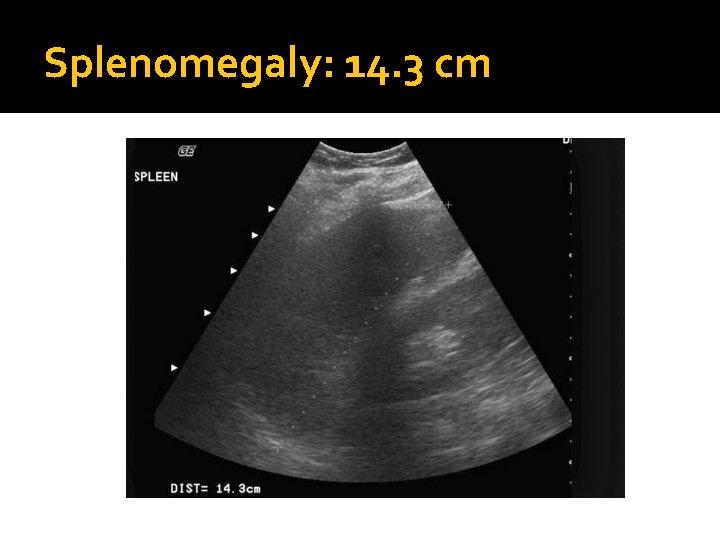

Splenomegaly �Splenomegaly is indicated with a longitudinal measurement > 12 cm or if the spleen is inferior to the lower pole of the left kidney.

Splenomegaly: 14. 3 cm